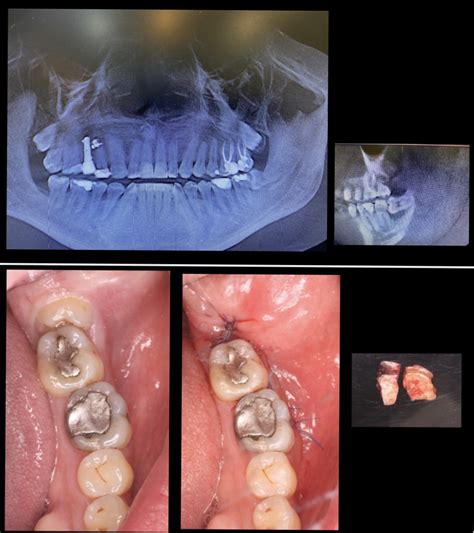

- Extracción simple: Se practica con muelas ya erupcionadas sin intervenir en la encía o el hueso. La muela se ‘ahueca’ (fase de luxación) y se extrae tirando de la corona con unos fórceps dentales.

- Extracción con cirugía: Es la que se emplea cuando las muelas están impactadas o dañadas. Implican la realización de una incisión en la encía y, en ocasiones, en el hueso. Este procedimiento corre a cargo de un cirujano maxilofacial y requiere de más tiempo y precisión que el de la exodoncia simple.

- Extracción de la muela: Una vez estés bien anestesiado (comprobamos que no sientes dolor antes de empezar), procedemos a extraer la muela del juicio. Si es una extracción simple, el proceso es bastante directo: utilizamos un instrumento llamado elevador o botador para aflojar el diente con movimientos suaves, y luego unas fórceps (pinzas dentales) para sujetar la muela y sacarla con cuidado. Sentirás presión y movimiento, pero nada de dolor. Muchas veces la muela sale completa de una vez. En cambio, si la muela está impactada o sale en mala posición, la extracción se vuelve quirúrgica: haremos una pequeña incisión en la encía para descubrir la muela. Es posible que necesitemos remover un poco de hueso alrededor con una fresa (un torno especial) para liberar el diente. A veces también cortamos la muela en partes más pequeñas para sacarla por secciones, especialmente si la corona (la parte de arriba) es grande o las raíces están enganchadas. Todo esto suena aparatoso, pero recuerda: tú estarás anestesiado localmente, no sentirás dolor, solo los movimientos y vibraciones.

- Cierre y cuidados inmediatos: Cuando la muela del juicio ya está fuera, queda una pequeña herida en la encía (y a veces un espacio en el hueso). Si fue una extracción simple, normalmente no hace falta dar puntos; la herida es pequeña y tu propia sangre formará un coágulo que protege y empieza la cicatrización. En extracciones quirúrgicas, colocaremos puntos de sutura (muchas veces puntos reabsorbibles que no hay ni que quitar; otros se retiran en aproximadamente 7 días). Tras la extracción, se coloca una gasa sobre la zona y te pediremos que la muerdas firmemente durante 20-30 minutos. Esto ayuda a contener el sangrado inicial y a que se forme el coágulo correctamente.